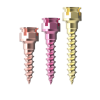

Арт:

307-1010

Арт:

307-1012